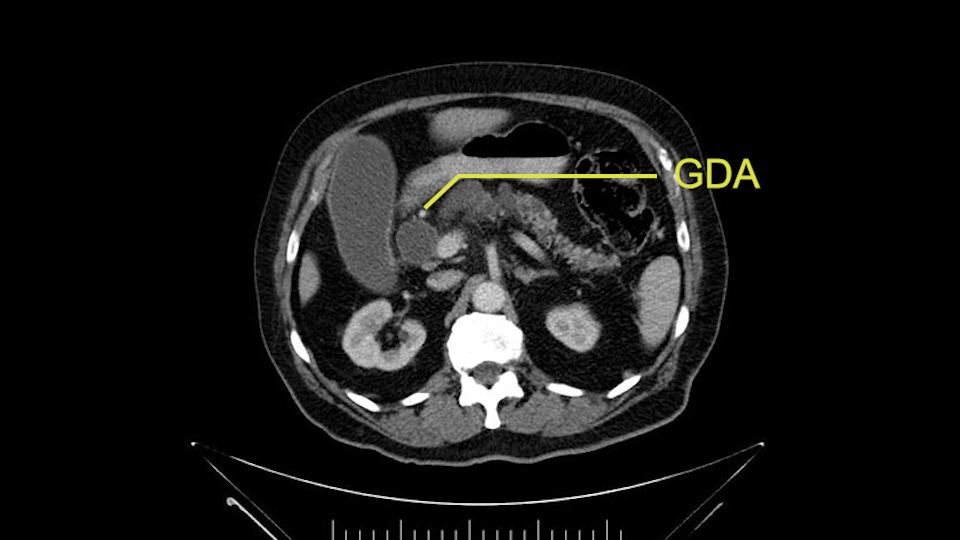

The gastroduodenal artery, a major artery that we have to divide, along with some pancreatoduodenal arteries, may have atherosclerotic changes so they would have to be handled with care, when I attempt what I think would be a pylorus-preserving pancreatoduodenectomy would be the plan. In some cases, I might make an intraoperative change and do a partial antrectomy or a pylorus-resecting Whipple, should the need arise for technical reasons but not because of the size of the tumor.

The other slowing down moment would be the gastroduodenal artery. Confirming that the gastroduodenal artery is not a dominant artery supplying blood to the liver. Liver failure is something which we don’t want due to altered blood supply to the liver or hampered arterial blood supply to the liver. So I would dissect out the hepatic artery, the left and right branches very clearly. Put a bulldog clamp on the gastroduodenal artery, make sure that the perfusion of the liver is excellent on the right and left side, and then divide the gastroduodenal artery. I would avoid using crushing instruments or crushing clamps on the gastroduodenal artery because they have a tendency to shatter in patients who are old with friable vessels so you have to be careful and tackle it with the help of a 5-0 or a 6-0 prolene sutures. In younger patients, I would just apply clips and move on when it comes to dividing the gastroduodenal artery.

I am a believer in pylorus preservation. And in this case I see no reason why that wouldn't be possible. Mobilize the duodenum, divide the gastroepiploic vessels and divide the duodenum. I try to divide it with a linear stapler about four centimeters from the pylorus to have adequate length for my GI anastomosis. This facilitates exposure of the head neck of the pancreas. I find the gastroduodenal artery. This patient has normal arterial anatomy. Always on every preoperative CT scan I look to see if there is a replaced right hepatic. In this case I did not see one. Regardless of how confident I am I always look carefully for variant anatomy. I always do a clamp test on the GDA before ligation. I doubly ligate the GDA with not just a tie but a suture ligature because of the risk of GDA blowout in patients with a leak.